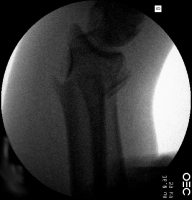

| Case 6 Extraarticular distal radius fracture with angulation and dorsal comminution. |

| Attempts at

closed reduction alone were unsuccessful. |

| Freer elevator

introduced percutaneously as a reduction aid. |

| Percutaneous

fracture stabilization with three pins via the

dorsal radial tubercle, radial styloid and FCR

portals. |

| Pins were left

protruding and bent to overlap. |

| Thermoplastic-pin

construct at 6 weeks, immediately prior to removal. |